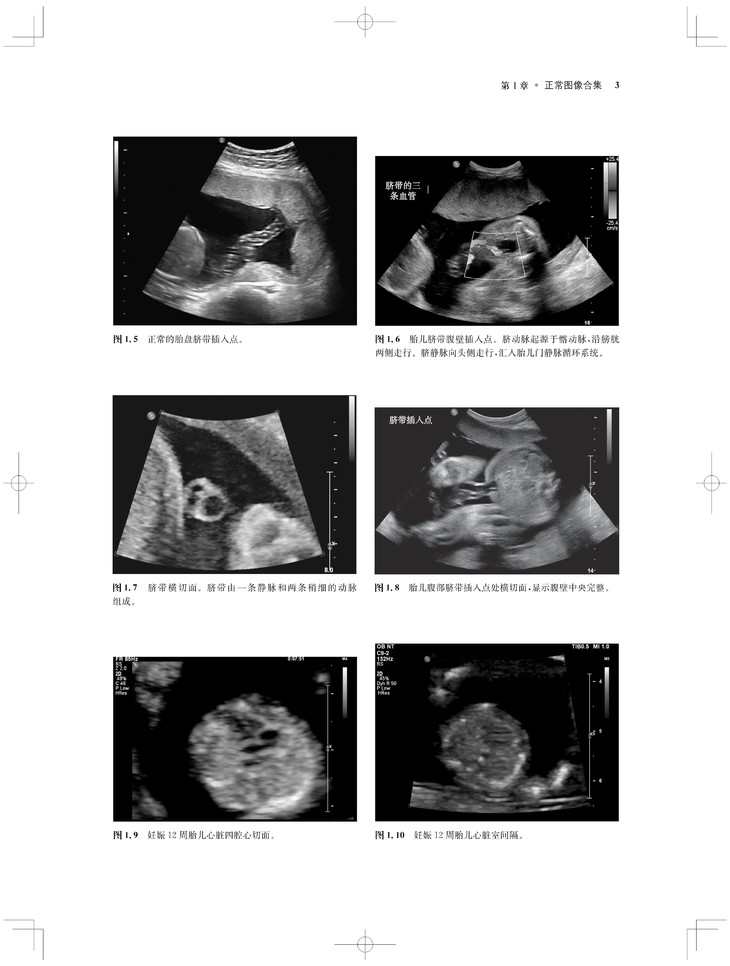

内容涵盖了胎儿宫内疾病的所有病种,从疾病的概述、流行病学、病因学、病理生理学,到临床表现、各类影像学技术的诊断和鉴别诊断,再到产前、产后的治疗和干预手段,都做了全面介绍,重点阐述了疾病的超声、X线、CT、MRI、PET、CT等影像学表现,以及诊断与鉴别诊断,并辅以大量标准化的影像学图片,图文并茂。

《产科影像学——胎儿诊断和监护》是Elsevier(Saunders)出版的“Expert Series”之一,由国际最顶尖的妇产科、生殖科、母胎医学和影像学专家共同编写,代表着该领域最顶尖的水平。书中配有大量典型影像图片,内容丰富全面,编写理念先进,侧重于疾病的影像学征象分析及鉴别诊断和诊断流程的制定,从临床思维上进行了更新;同时兼顾临床和病理医师,重点内容以列表、提要、要点的形式进行总结,提纲挈领,方便读者阅读、记忆。对于每天不断进行诊断与鉴别胎儿疾病的影像工作者、病理科和临床医师而言,具有重要的参考价值。